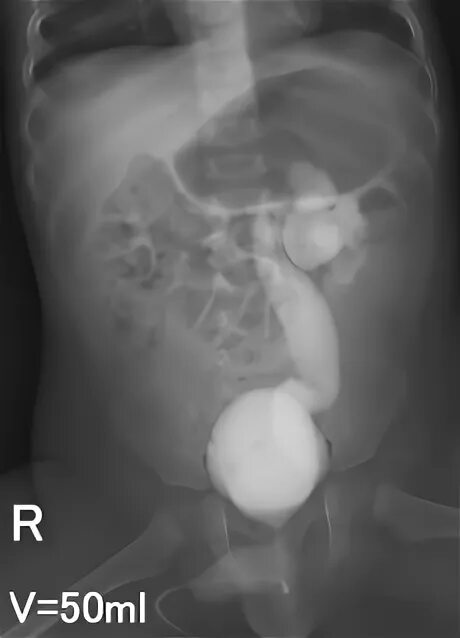

Мегауретер у детей что это